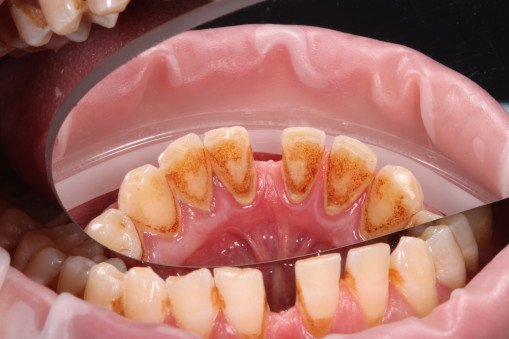

А прежде, чем вы посмотрите фотографии «до» и «после» лечения слизистой оболочки полости рта, проведенных в нашей клинике, хочу поблагодарить большое количество наших пациентов, которые поверили, прониклись нашей концепцией, и мы вместе, именно вместе победили болезни десны, гингивит и пародонтит!

До/после лечения